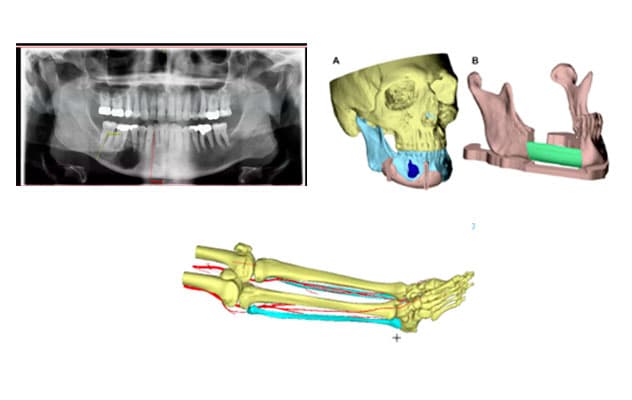

X-ray and virtual models

The images show a panoramic X-ray of an ameloblastoma tumor in the lower right mandible; virtual models of the resection planes around the tumor (A) and the area of fibula free-flap insertion (B); and leg detailing fibula anatomy and blood vessel location.

The first step of planning surgery was CT imaging of the head, face and area from which the free flap would be taken — in this case, the fibula. CT angiography of the leg also ensured the patient had the appropriate blood vessel anatomy to allow for fibula free flap harvest, since the procedure requires removing one of the three main arteries to the foot for use in the reconstruction.

"We worked with biomedical engineers in Mayo Clinic's 3D Anatomic Modeling Laboratories to load the CT images into the software and convert them into 3D virtual models in a process called segmentation," says Dr. Ettinger. "The software can color-code the different anatomical structures and produce images that the surgeon can virtually move and view from any angle."

Dr. Ettinger used the software to establish the virtual cutting planes with 1-centimeter margins around the tumor. He also planned the reconstruction based on fibula architecture and blood vessel location.